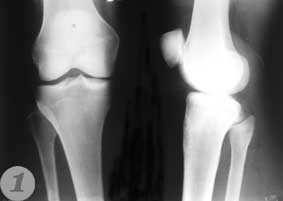

1 - до артроскопической операции пластики передней крестовидной связки коленного сустава